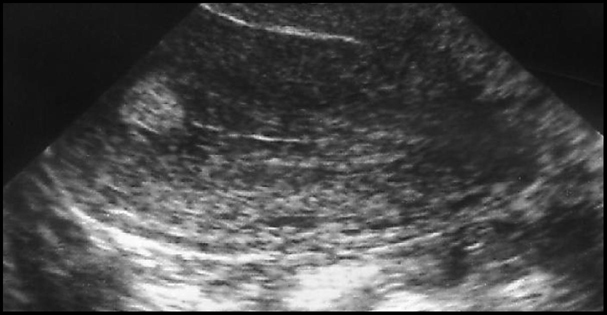

Polype muqueux. Hyperéchogène, avec ou sans renforcement postérieur et petites zones kystiques

5 à 15 mm. Arrondis ou ovalaires. Ligne cavitaire intacte tant qu’il se trouve dans l’épaisseur de la muqueuse